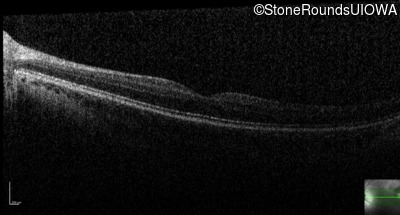

Congenital Stationary Synaptic Dysfunction (IA2g)

Age at visit:

13 years

OD

OS

20/63 -2 sc

20/63 -2